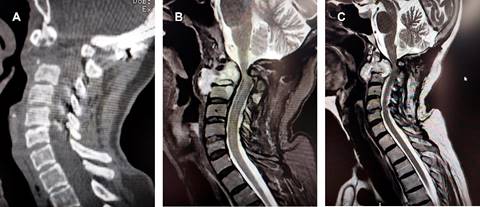

Paciente femenino de 62 años, con antecedente de bocio, manejada con tiroidectomía total por oncología, con reporte histopatológico de bocio, sin presencia de tumor. Acude dos años después con dolor cervical principalmente a las rotaciones; la resonancia magnética (RM) mostró lesión lítica de odontoides y cuerpo del axis; se le practicó fijación posterior occipitocervical (Figura 1). La biopsia resultó negativa para tumor. Diez meses después presentó cuadriparesia de 40%, hiperreflexia, asociados a signos de Hoffmann y Babinski bilateral y dolor radicular C5 al movimiento, sensibilidad conservada en las cuatro extremidades, y exacerbada en territorio C5 izquierdo. La radiografía lateral de columna cervical mostró destrucción de odontoides y parte del cuerpo de C2 (Figura 2A); en la RM se observa lesión destructiva invadiendo canal medular, así como desplazamiento de tráquea y esófago (Figura 2B y C). Se practicó mediante abordaje anterolateral cervical alto y microscopio la resección parcial de la lesión (aproximadamente 3 cm2). El reporte de patología indicó: carcinoma folicular tiroideo bien diferenciado metastásico. La evolución postoperatoria de la paciente fue satisfactoria, con recuperación de la cuadriparesia, se canalizó a tratamiento con yodo radioactivo y radioterapia.

Figura 1: Imágenes de resonancia magnética en cortes (A) sagital y (B) axial que muestran lesión lítica de odontoides y cuerpo del axis. C) Radiografía simple lateral de columna cervical en la que se observa fijación posterior occipitocervical.